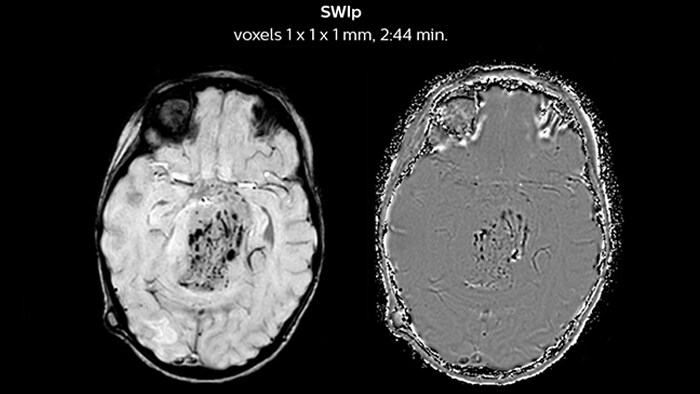

“We have been very, very pleasantly surprised by the quality of the images,” says Dr. Mahajan. “I have shown Prodiva images to people around the world during my travels.” Ingenia Prodiva 1.5T includes such features as dStream digital broadband technology to increase image quality with high SNR. “The system came with its newest sequences that allow us to perform advanced techniques like excellent diffusion in the brain and other body parts as well, spectroscopy, detailed neurography, CSF flow studies, imaging of difficult areas like skull base, tractography, DTI, and even DTI of the spinal cord – all of this is available to us.” The radiologists at Mahajan Imaging were also impressed by the quality of cardiac MRI. “We have done some MR angiography of the coronary arteries with the Prodiva and it provided excellent coronaries – and this was without using any contrast agent. We can also perform fantastic ngiography of other body parts.” “With Prodiva 1.5T, the images are very crisp and sharp, and the resolution is very good,” says Dr. Mahajan. “Imaging can be done in short scan times with excellent quality and broad range of possible applications, whether it is angiography, a scan with 3D reconstruction, any kind of more special images, what we do, the sharpness, resolution and the ease of use – everything counts in total when we are reporting.”